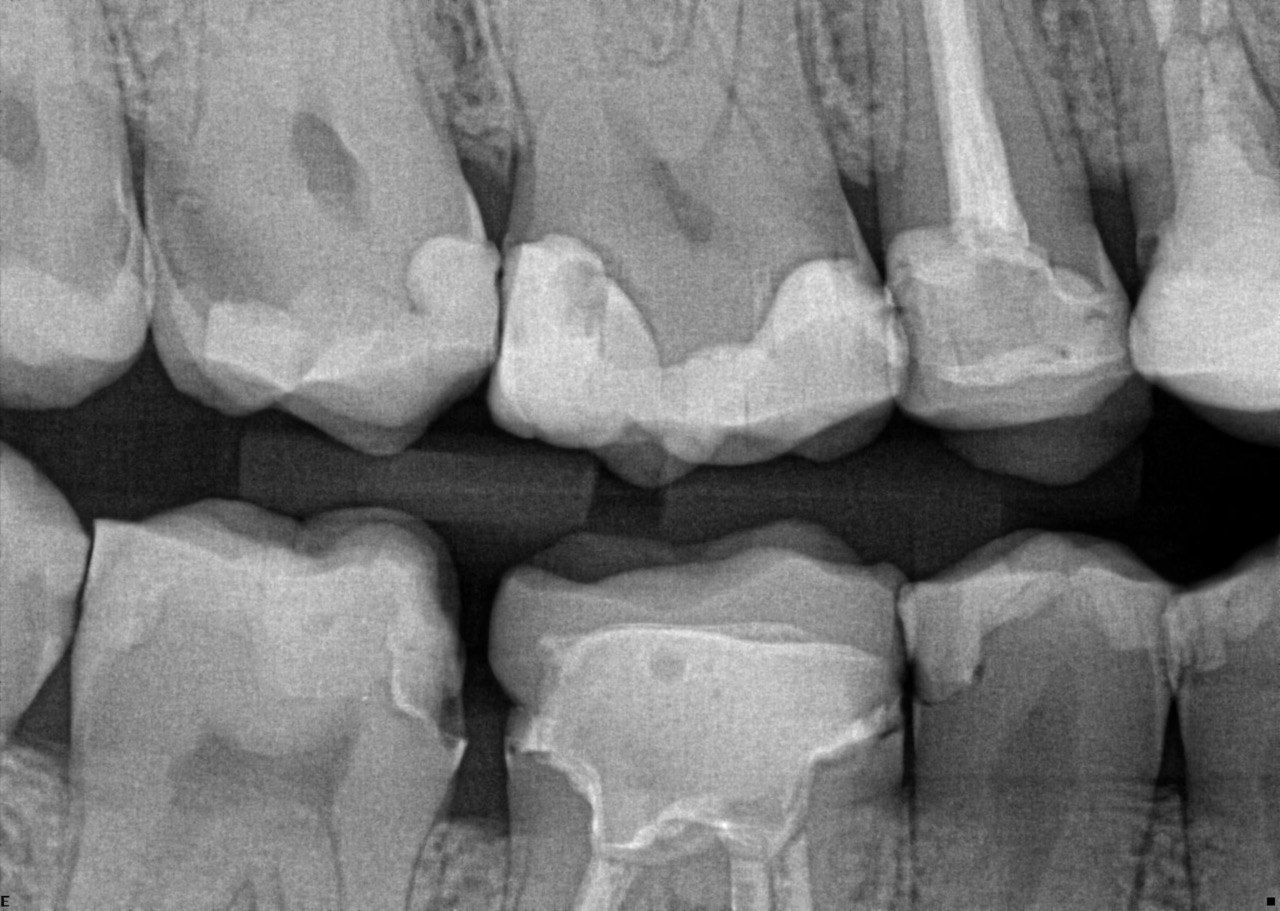

Question 26: What is the option explaining the distal surface of the tooth # 2.6 and mesial surface of the tooth # 2.7 respectively?

Question 27:  What is the option explaining the distal surface of the tooth # 2.5 and distal surface of the tooth # 2.4 respectively?

Question 28: What is the option explaining the distal surface of the tooth # 2.5?

Question 29: What is the option explaining the Mesial surface of the tooth # 2.5 and distal of tooth # 2.4 respectively?

Question 30: What option can be seen on the lower jaw of the following X ray?

Question 31: Which options can be selected for the following X ray?

Question 32: Which surface need restoration?

Question 33: What is the condition in mesial of tooth # 4.6?

Question 34: What is the level of caries on mesial of the tooth # 1.6?

Question 35: Which surface shows recurrent caries?

Question 36: What is the caries on distal surface tooth # 1.5?

37: What is the caries on mesial surface of tooth # 2.6 and distal surface of tooth # 2.5 respectivel?

38. What is the condition of the distal surface of tooth # 1.4 and mesial tooth surface tooth # 1.6?

39. What is the caries on distal tooth # 2.6 ?

40. What is the caries on mesial tooth #3.6 ?

41. What options can be selected for the following X ray?

42. What is the caries on mesial surface of the tooth # 3.6?

43. Which surfaces require restoration?

44. What is the condition on distal surface of the tooth # 4.4?

45. What is the condition on mesial surface of the tooth # 1.5?

46. which teeth shows evidece of occlusal recurrent caries?

47. Which option does not describe the X ray bellow correctly?

48. Which tooth shows recurrent caries?

49. Which surface shows a RA1 caries?

50. Which option is evident on the print of the X ray?